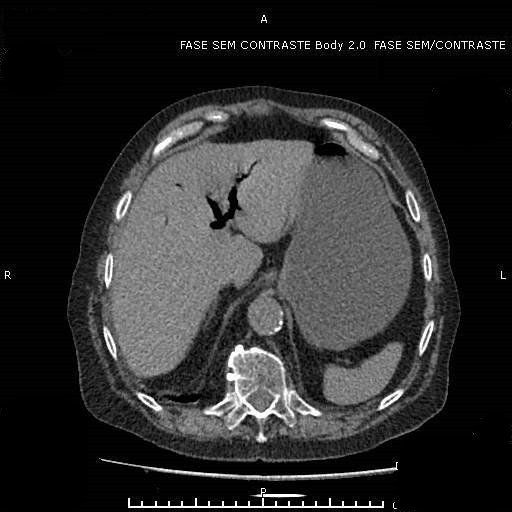

Achados de Imagem

- Pneumobilia - presença de ar nas vias biliares.

- Visualização do calculo no íleo terminal.

- Obstrução intestinal.